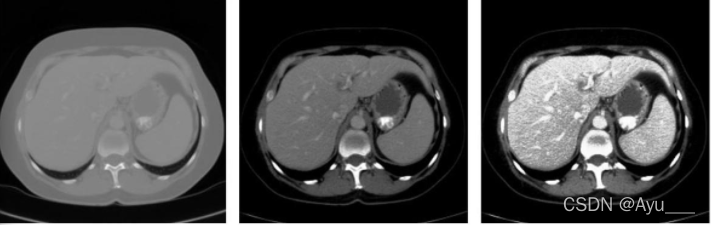

- 原始切片的Hounsfield单位范围为-100-400hu,忽略了不感兴趣的器官和组织。

- 进一步实验直方图均衡化,增强异常组织的对比度。

- 第二步:两个级联的完全卷积神经网络首先第一个U-Net分割肝脏,然后第二个U-Net从第一步分割的肝脏感兴趣区域(ROI)中学习分割病变。